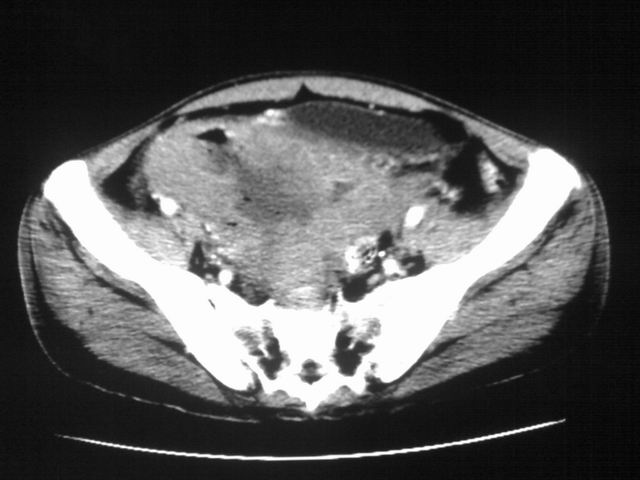

患者m 56岁,盆腔及下腹部胀痛半年,加重1月余,消瘦\中重度贫血.(附:平扫时直肠的高信号为,残留的钡剂).补一下病史:胃镜及纤维结肠镜均无明显异常.

首先是病灶的定位,平扫看很象肠管肿瘤但既然纤维结肠镜正常就可以除外结肠病变,增强成不均匀强化,位于右下腹部应该首先考虑回肠末段占位性病变,1淋巴瘤,2间质瘤,3腹膜后神经原肿瘤待除外,

首先是病灶的定位,平扫看很象肠管肿瘤但既然纤维结肠镜正常就可以除外结肠病变,增强成不均匀强化,位于右下腹部应该首先考虑回肠末段占位性病变,以间质瘤或淋巴瘤可能性大.,

膀胱及直肠间有不规侧的软组织密度影,内密度不均匀。其内有坏死囊变,前列腺及精囊腺,膀胱后壁受浸。结合病史考虑腹膜后肉瘤可能性大。